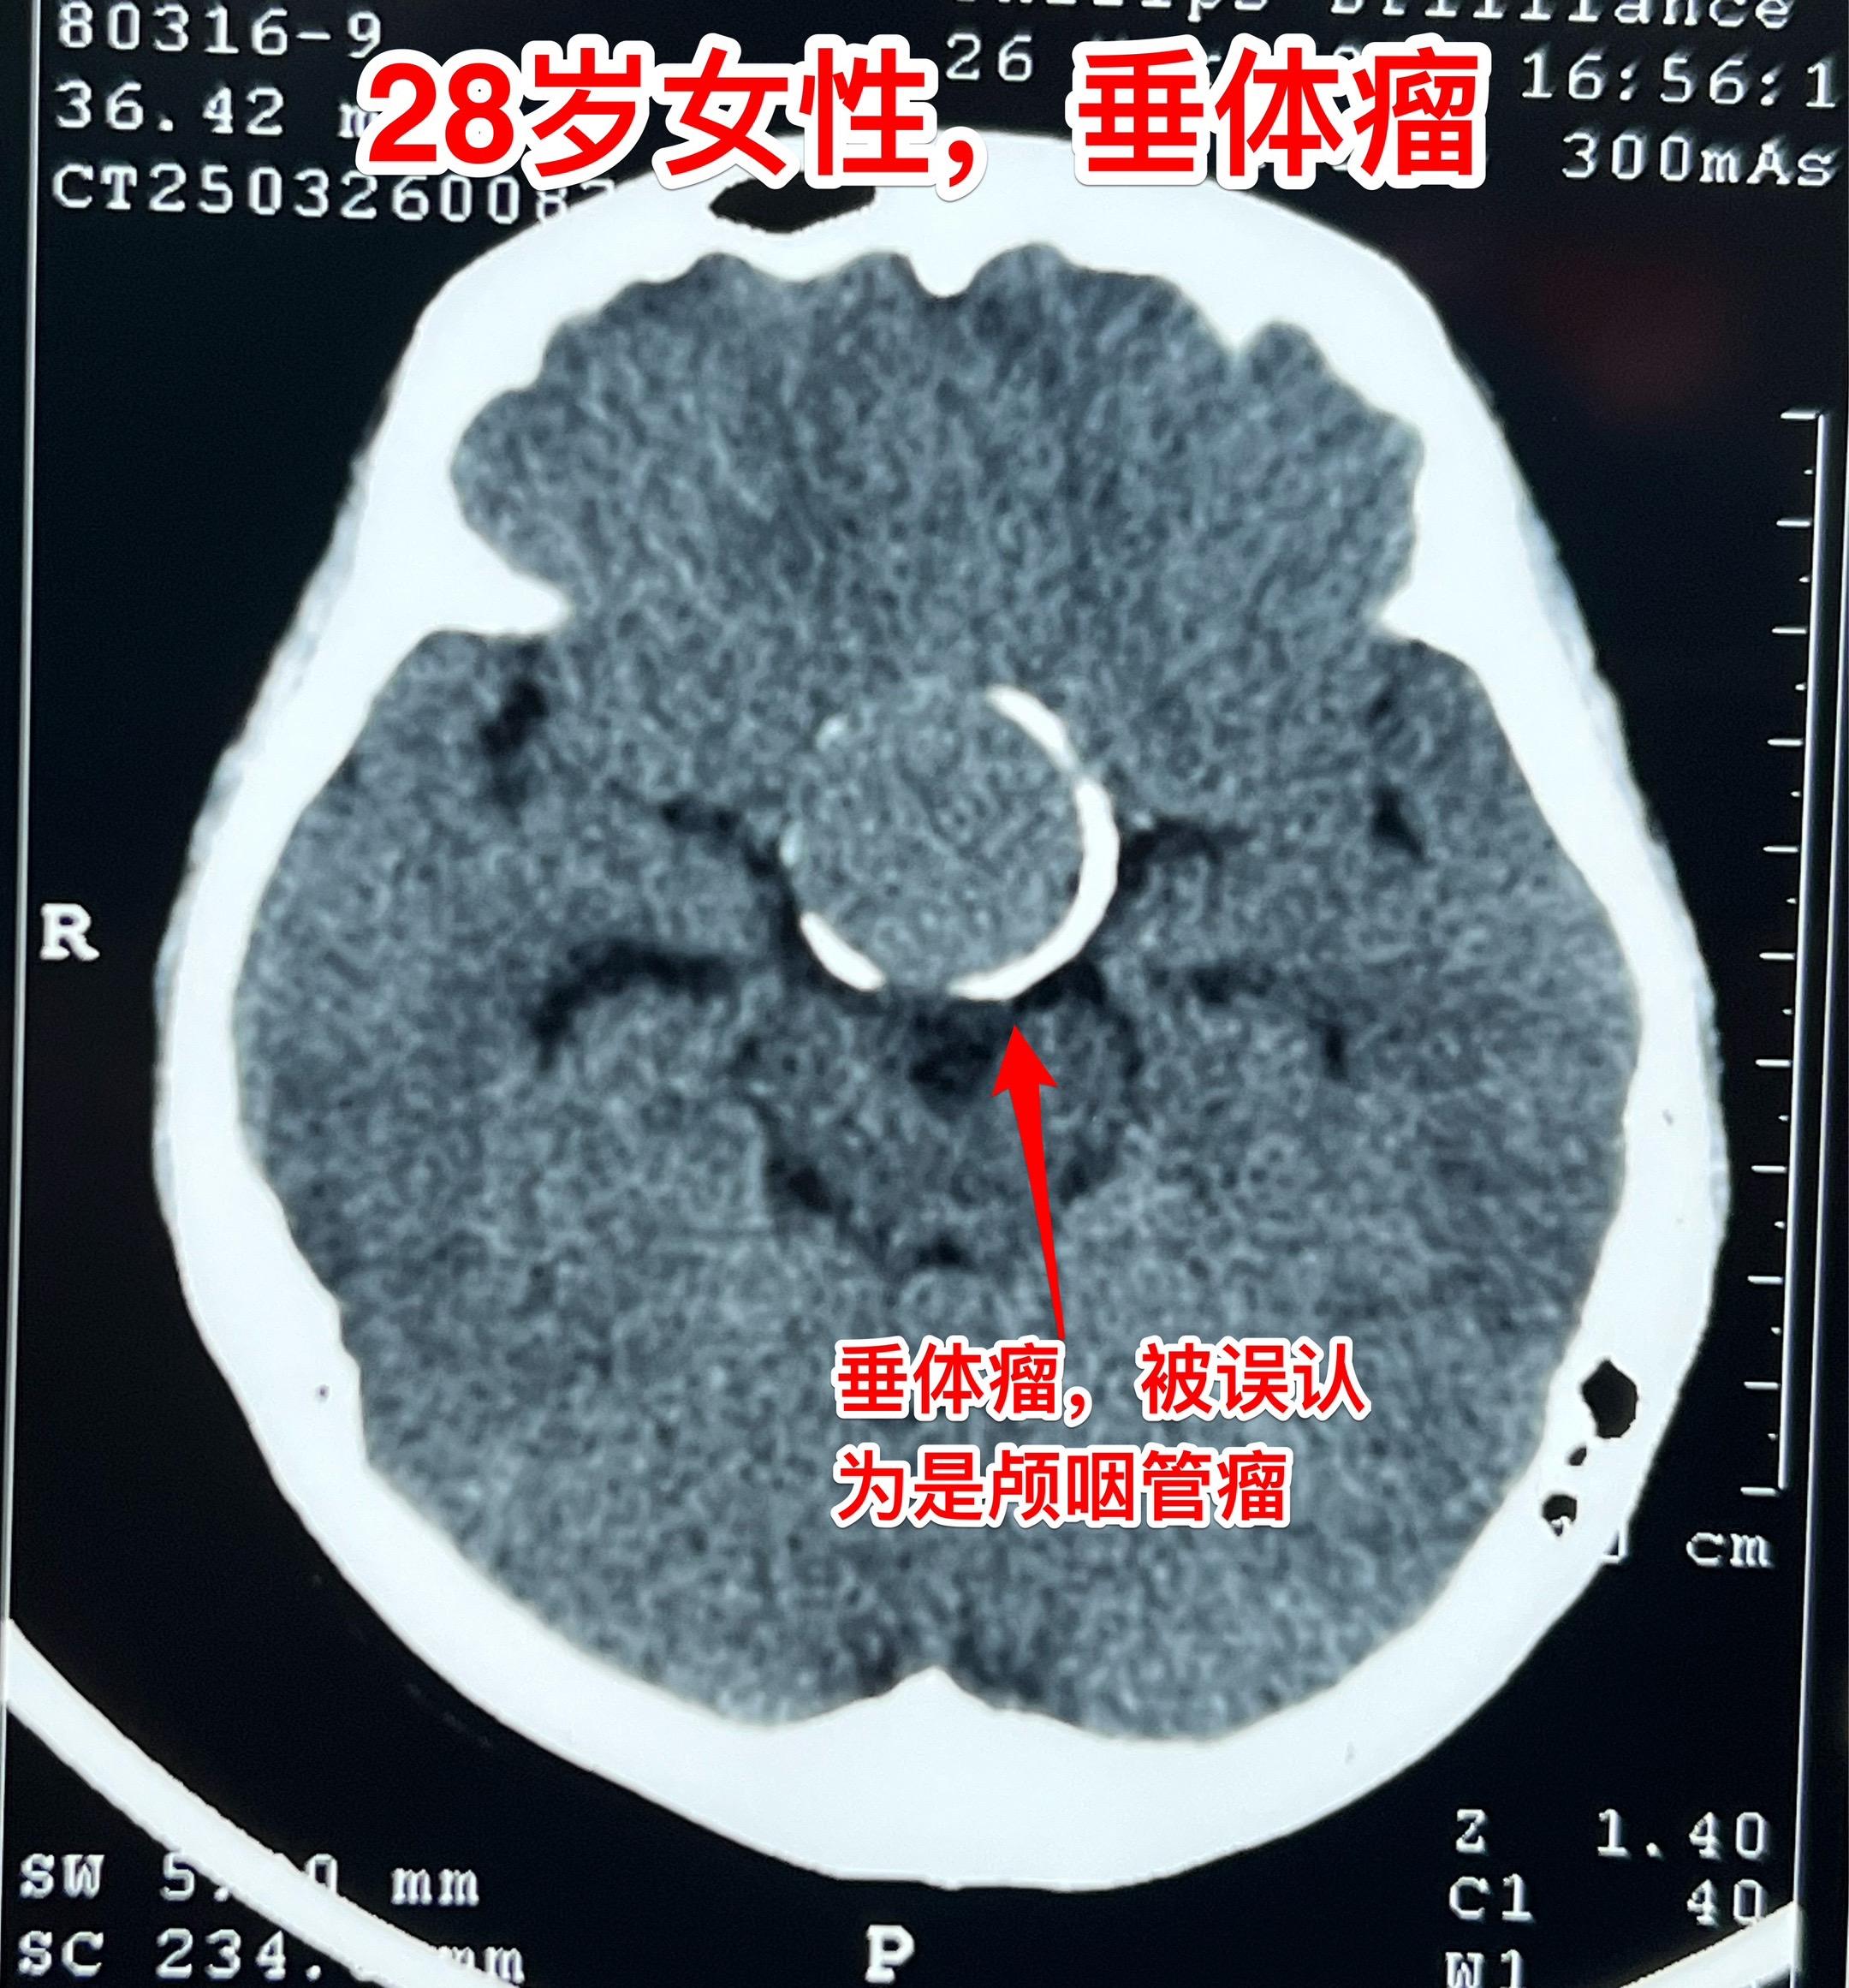

28岁女性6年前生完孩子就一直内分泌紊乱。山西省晋城市28岁女性,6年前生完孩子就一直没有生理周期,而且渐渐出现身体消瘦,视力下降。 作磁共振和CT发现脑部有一个巨大肿瘤,肿瘤周边似乎有钙化,见图3,怀疑为颅咽管瘤,就到北京三博脑科医院找我看病。 其实这个肿瘤是垂体瘤,肿瘤呈“顶天立地”状。化验激素显示TSH、T3、T4均高于正常,也就是说有甲亢。这是罕见的分泌TSH的垂体腺瘤。病人体重才80多斤! 今天是周日,加班为她作了手术。